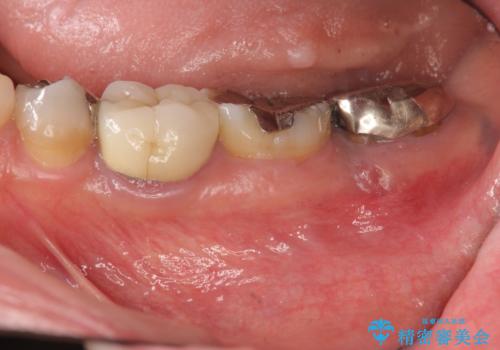

深い虫歯により抜歯となった奥歯 インプラント治療でかみ合わせを回復する